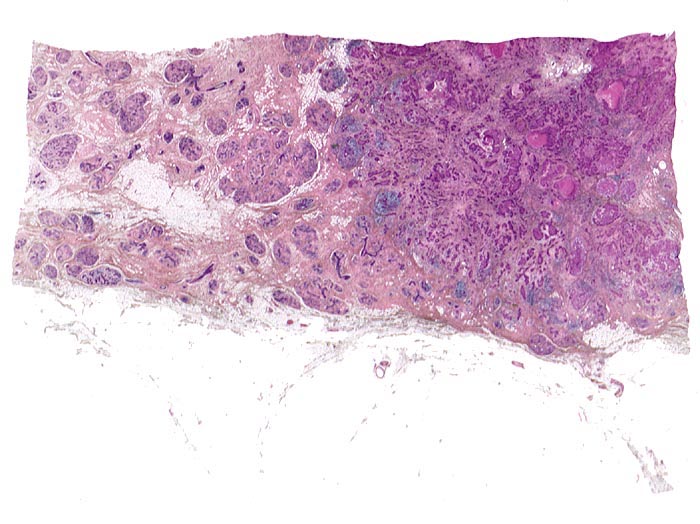

•  Invasives duktales Karzinom mit desmoplastischem Stroma rechts unten im Präparat.

•  Die Karzinominfiltrate bestehen aus schmalen soliden Zellsträngen, die keine Drüsenlumina ausbilden. Eine Myoepithelschicht fehlt. Kein assoziierter Mikrokalk.

• Mässig zahlreiche Mitosefiguren und Apoptosen.

• In den bindegewebigen Ausläufern dilatierte Gangstrukturen mit peritumoralem duktalem Carcinoma in situ mit hohem Kernmalignitätsgrad (Grad 3, kribriformer und solider Typ mit Komedonekrosen, kein assoziierter Mikrokalk). Erhaltene Myoepithelschicht im Bereich des in situ Karzinoms.

• Läppchenkanzerisierung (Ausbreitung des Karzinoms in den Azini der Drüsenläppchen).

• Peritumorale Arterie mit assoziiertem dilatiertem Lymphgefäss mit intraluminalem Tumor (Lymphangiosis carcinomatosa).